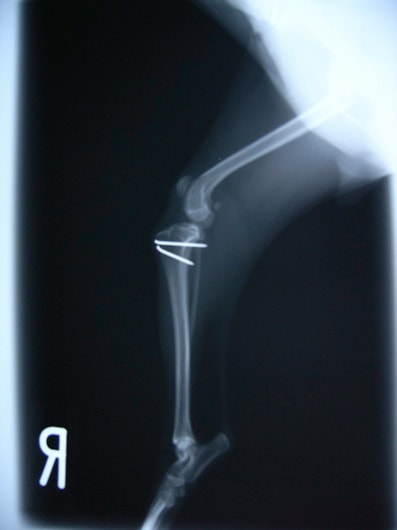

■ 症例22 ポメラニアン 1歳5か月 去勢雄

左後肢の挙上を主訴に来院した。整形学的検査、レントゲン検査より左右の膝蓋骨脱臼(左GradeⅡ〜Ⅲ、右Grade Ⅱ)を認めた。また、脛骨の前方引き出し試験の際に、引き出し兆候は認められないものの、疼痛が認められたため、前十字靭帯の損傷が疑われた。術中における、目視および関節内の操作によって、前十字靭帯の損傷や過伸展といった異常が認められなかったため、膝蓋骨脱臼の整復のみ実施した。手術手技は縫工筋及び内側広筋の解放、脛骨粗面の外側転位、滑車ブロック形造溝術、内外側関節包の縫縮を実施した。本症例は跛行もなく経過良好である。しかし、頸骨高平部の角度(TPA)が 右26.2°、左24.9°であり、解剖学的に前十字靭帯損傷のリスクが高いことから今後の経過に注意が必要である。